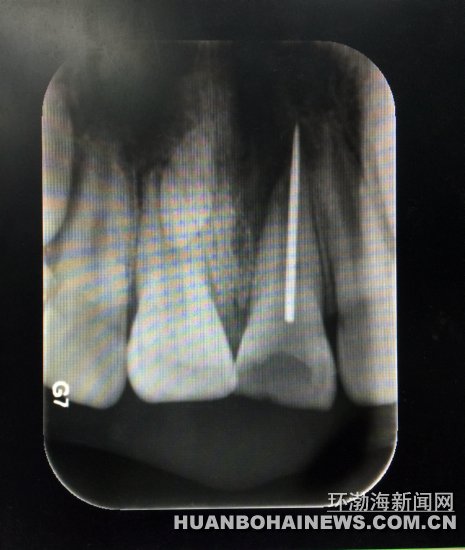

X光片顯示縫衣針扎入牙齒根管。 醫(yī)生取出的縫衣針。 近日,9歲的淘淘(化名)在玩耍時(shí)誤將縫衣針扎入門牙根管中,市協(xié)和醫(yī)院口腔醫(yī)院醫(yī)生利用顯微鏡下根管異物取出術(shù),從這名熊

X光片顯示縫衣針扎入牙齒根管。X光片顯示縫衣針扎入牙齒根管。

該院牙體二科任宏宇醫(yī)生接診后,結(jié)合牙片發(fā)現(xiàn)這名小男孩左上門牙根管里扎有一根斷針。孩子牙齦紅腫疼痛,煩躁不安,家長十分著急。

淘淘說,自己拿著媽媽的縫衣針給門牙里的牙洞“撓癢癢”,可玩著玩著針就斷了,半截針扎進(jìn)了門牙里。醫(yī)生隨即施以顯微鏡下根管異物取出術(shù)。10幾分鐘后,一根2厘米左右的斷針從孩子的左上門牙根管里順利取出。原來,孩子嘴里這顆扎進(jìn)斷針的牙齒是有齲洞的齲齒,孩子玩針時(shí)才誤將鋼針扎進(jìn)牙的根管里。